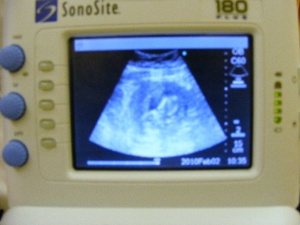

The 5th January 2010 we had our next scan, I was then 10 weeks pregnant, no morning sickness, in fact apart from the cold I felt fine, no symptoms at all of being pregnant, the scan was great and we could now see that now it wasn’t just a blob it was in fact a baby (maybe more like a tadpole), all fine with baby, measurements where spot on, since I was very nervous with this pregnancy the midwife arranged another scan in four weeks.

Teresals2ndscan Pics 001.jpg